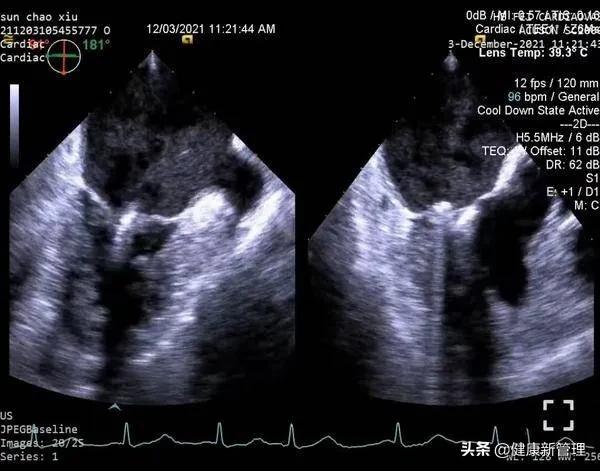

术前心脏彩超完善各项术前准备后,患者于全麻下,梅举教授主刀,经食道超声引导,经心尖送入二尖瓣夹,捕获并夹合二尖瓣前后叶病变处,二尖瓣夹位置稳定。术后超声显示,该患者二尖瓣反流即刻减少。

二尖瓣夹系统植入术后